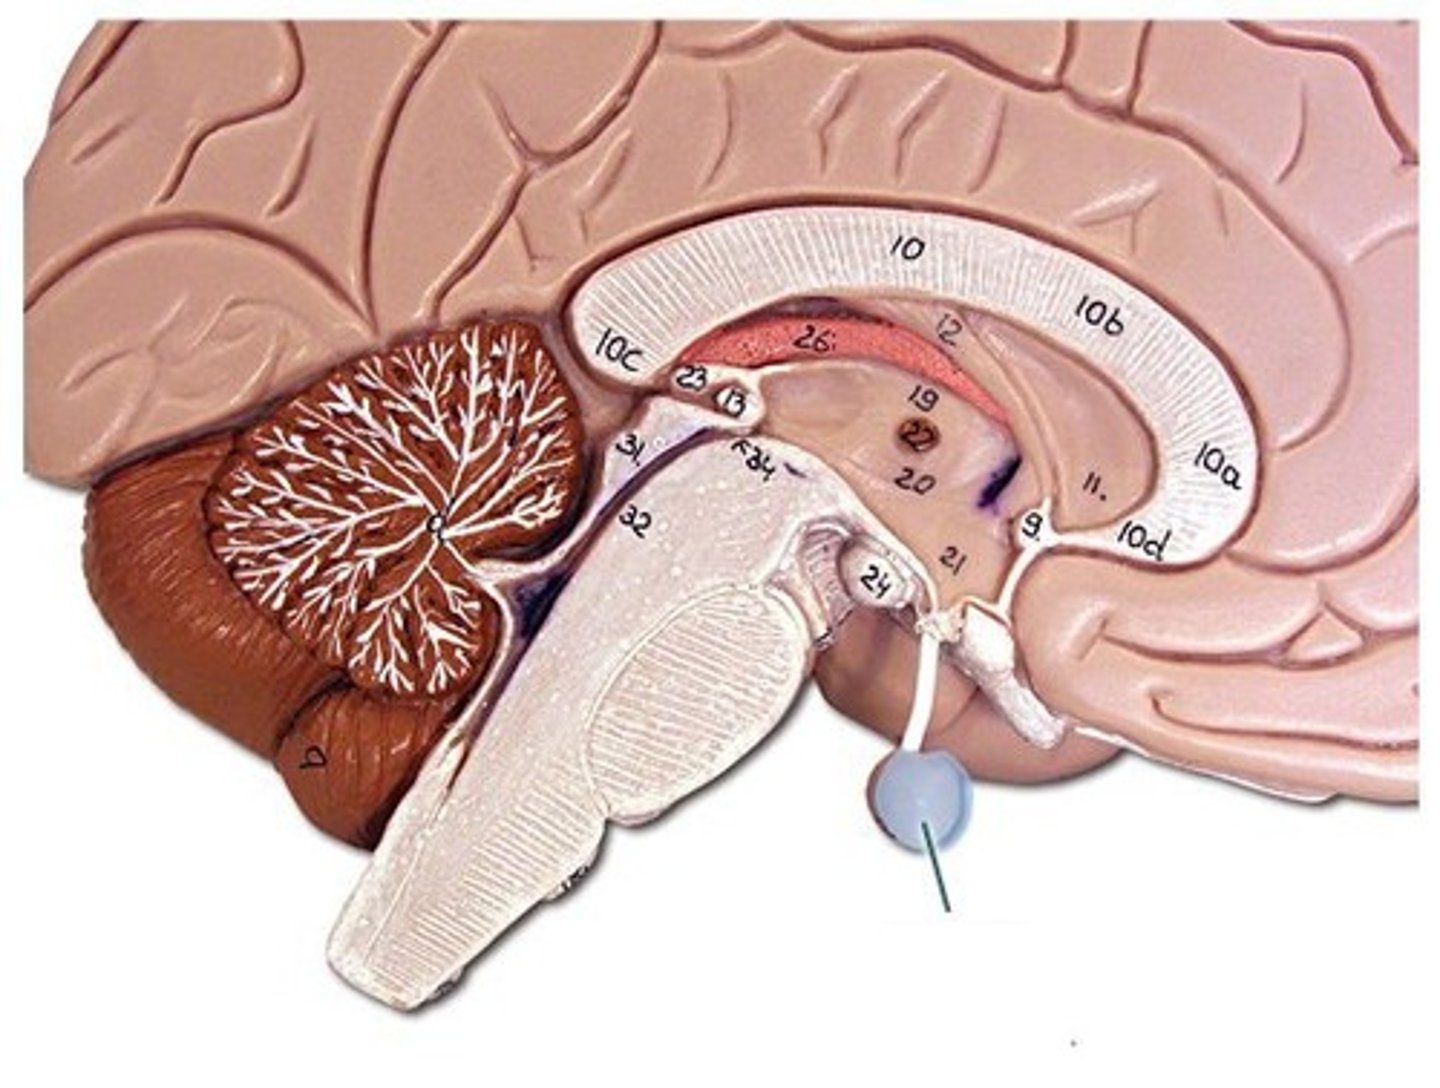

brainstem

cerebellum

cerebrum

hypothalamus

medulla oblongata

lateral ventricles

midbrain

pons

thalamus

corpus callosum

fornix

cerebral aqueduct (brainstem)

corpora quadrigemina (brainstem)

fourth ventricle

hypophysis (pituitary gland)

infundibulum

intermediate mass of thalamus

pineal gland

choroid plexus (of ventricles)

third ventricle